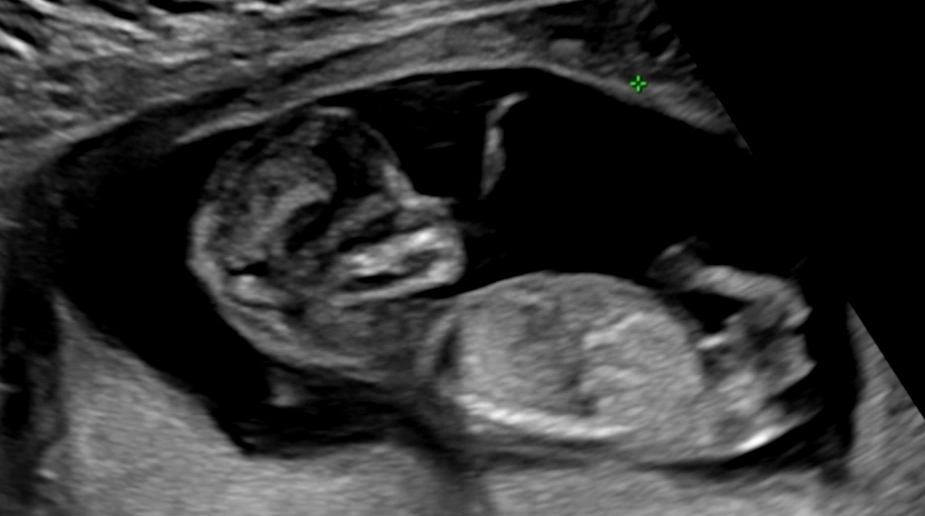

12주차 6일 초음파사진, 성별 궁금해요~

1차기형아검사 걱정 했는데, 무사통과했네요! 병원에서는 16주차에 성별 알려주신다 했는데, 그전까지 넘 궁금해서 올려봐요~